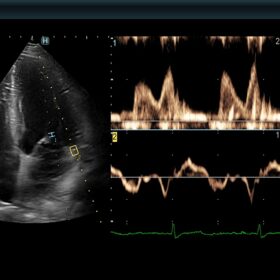

Ultrasound ARIETTA 850 SE – Image Gallery and Videos

Cardio 2D and Color mode

Radiology 2D and Color mode